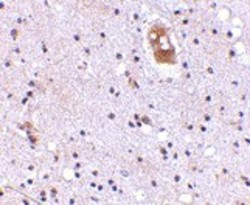

Supportive validation

- Submitted by

- Acris Antibodies GmbH (provider)

- Main image

- Experimental details

- Immunohistochemistry of EVER2 in human brain with AP30323PU-N EVER2 antibody at 5 μg/ml.